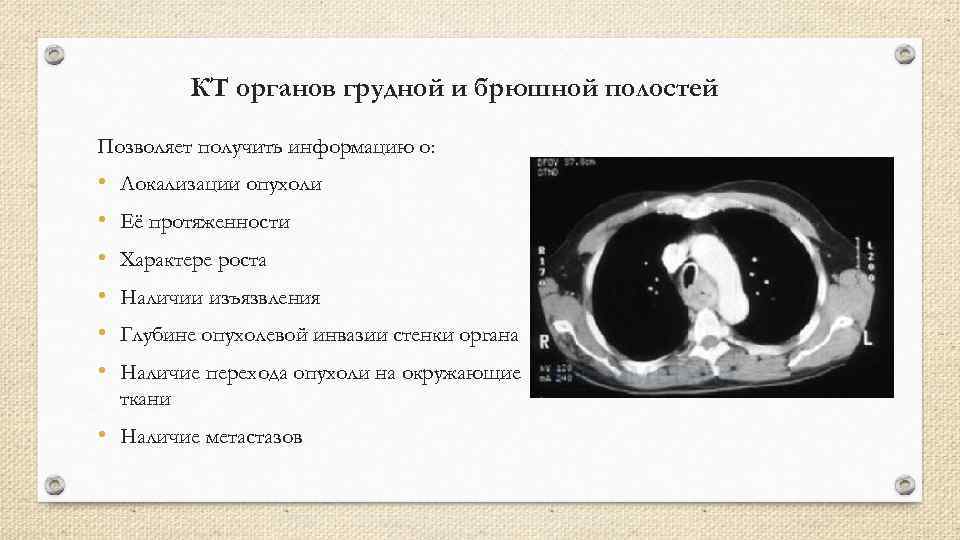

КТ органов грудной и брюшной полостей Позволяет получить информацию о: • • • Локализации опухоли Её протяженности Характере роста Наличии изъязвления Глубине опухолевой инвазии стенки органа Наличие перехода опухоли на окружающие ткани • Наличие метастазов

КТ органов грудной и брюшной полостей Позволяет получить информацию о: • • • Локализации опухоли Её протяженности Характере роста Наличии изъязвления Глубине опухолевой инвазии стенки органа Наличие перехода опухоли на окружающие ткани • Наличие метастазов